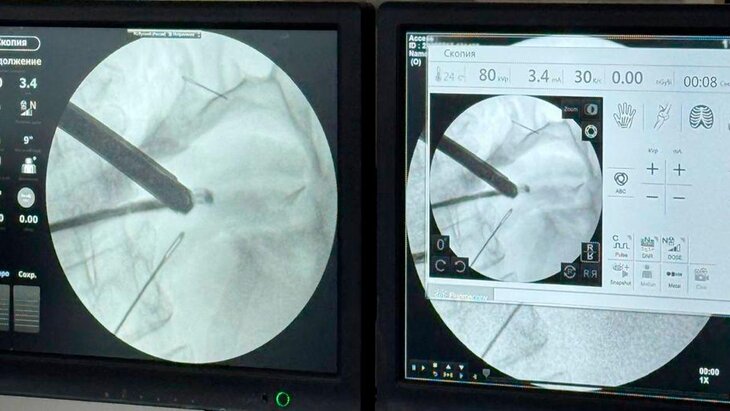

Врачи Красногорской больницы спасли 59-летнюю пациентку, которая проглотила 4 швейные иглы, сообщает телеканал "360".

Женщина поступила в больницу с болями в животе. Врачи при обследовании обнаружили ее в брюшной полости четыре швейные иглы. Пациентка рассказала, что проглотила посторонние предметы около месяца назад. За это время они успели частично обрасти тканями.

По словам заведующего первым хирургическим отделением Николая Мурашова, сначала хирурги планировали провести лапароскопию – операцию через небольшие проколы. Однако из-за открывшегося кровотечения пришлось перейти к лапаротомии – разрезу брюшной стенки.

В итоге все четыре иглы удалось извлечь. Уточнялось, что острые предметы проникли сквозь стенки желудка, а один из них достиг поджелудочной железы. Тем не менее орган удалось сохранить.